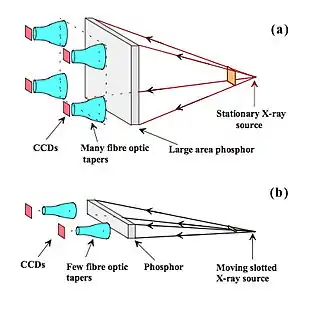

- Another technique for obtaining a digital image involves coupling a conventional phosphor screen to a Charge Coupled Device (CCD) using lenses or fibre optic coupling. The CCD matrix can be just 1,024x1,024 pixels in small field applications and systems have demonstrated limiting spatial resolutions of ~10 LP/mm. Larger fields of view can be achieved using an array of CCDs - see Figure 7.24, panel (a). When individual pixels are of size 40 μm and a detector area of 18x24 cm, an image matrix of 4,800x6,400 pixels results, which can provide a spatial resolution of 12.5 LP/mm. Broader area receptors have also found application in General Radiography, and digital implementation of Multiple Beam Equalization Radiography (AMBER) has been investigated[18].

Fig. 7.24: (a) A large phosphor screen coupled to several CCDs using fibre optic tapers; (b) A scanning-slot system where a narrow phosphor screen is coupled by the fibre optics to a few CCDs and the XRT/detector is scanned across the anatomy.

Fig. 7.24: (a) A large phosphor screen coupled to several CCDs using fibre optic tapers; (b) A scanning-slot system where a narrow phosphor screen is coupled by the fibre optics to a few CCDs and the XRT/detector is scanned across the anatomy.

- Another alternative is to use a slot scanning arrangement - see Figure 7.24, panel (b). Here, X-rays transmitted through the compressed breast produce light in a strip of CsI:Tl phosphor and this light is collected by the fibre optics and conveyed to the CCD arrays. Some features of this design are: